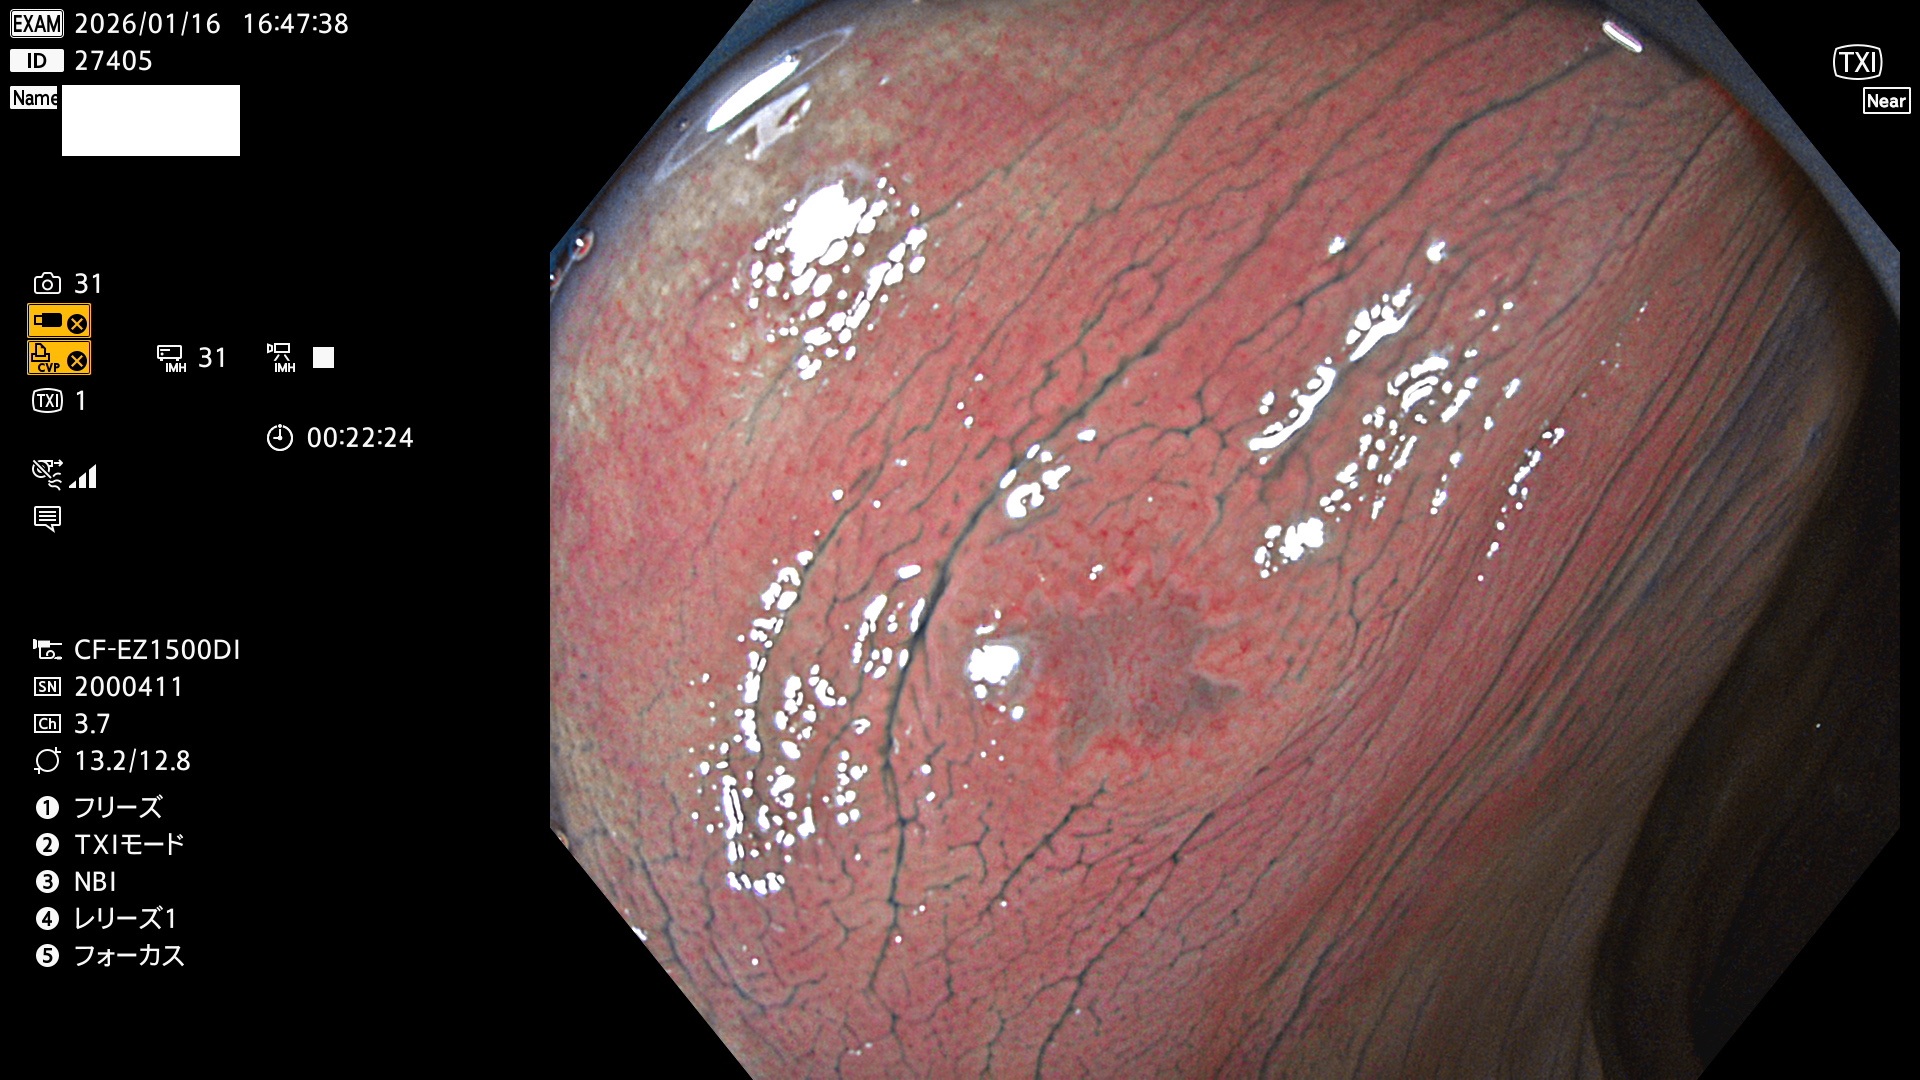

完全に平坦な物をUb、陥凹している物をUcと呼びます。Ubは認識が困難で、Ucはびらん(炎症)と紛らわしいために見落とされやすく、「内視鏡後・大腸癌」の原因になります。

毎週の検査(木・金・土・日)に発見されたUbとUc型・腺腫を、その週の日曜の夜にUPし1週間、提示します。

2026年1月15日〜1月18日の4日間(40件)5個 (Uc_ADR=5個/40人=13%)